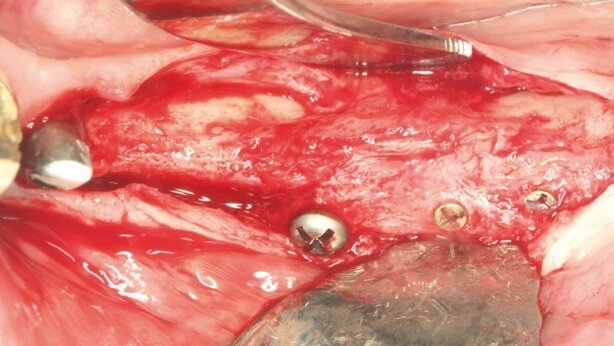

Po całkowitym obnażeniu podstawy kostnej (Ryc. 4), blok kostny został umieszczony i umocowany z pomocą 2 śrub do osteosyntezy (PSM medical solutions, D-Tuttlingen). Co więcej, został wykorzystany prototyp śrub samogwintujących. Głowy śrub zostały zagłębione na poziomie bloku kostnego i w ten sposób zostały wykorzystane jako punkt pomiarowy do określenia stopnia resorpcji w procesie gojenia (Ryc. 5). Aby uzyskać gładkie przejście przy brzegach bloku, te okolice zostały wypełnione granulatem kostnym pochodzenia wołowego (cerabone, Botiss Dental). Okolica augmentowana została następnie pokryta membraną osierdziową (Jason membrane, Botiss Dental, Ryc. 6). Po zakończeniu mobilizacji i adaptacji płata założone zostały szwy materacowe 6-0 wolne od napięcia (Premilene, Braun Melsungen, D-Melsungen, Ryc. 7).

Całkowita integracja bloku została osiągnięta po 6 miesiącach, co potwierdziło kontrolne zdjęcie rtg. Resorbcja materiału allogennego była nieznaczna (Ryc. 10 i 11). Bez konieczności dodatkowej augmentacji wprowadzono 3 implanty (Astra, Dentsply Implants, D-Mannheim, Ryc. 12 i 13). W czasie opracowania łoża dla implantów został pobrany materiał do biopsji. W badaniu histologicznym nowe ubeleczkowanie kostne zostało potwierdzone i tylko w kilku miejscach widoczny był wciąż trwający proces remodelingu (Ryc. 14).